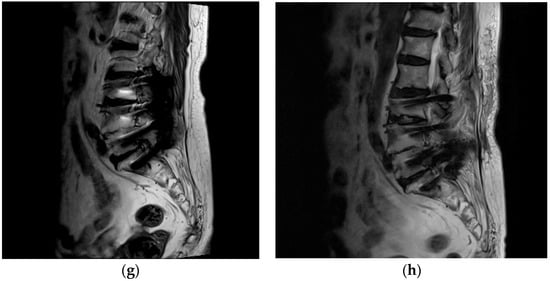

- Concordant imaging evidence of monosegmental FS at the same level within the fusion segment demonstrated on lumbar magnetic resonance imaging (MRI) and/or computer tomography (CT) scans;

2.2. Preoperative Work-Up

3. Results